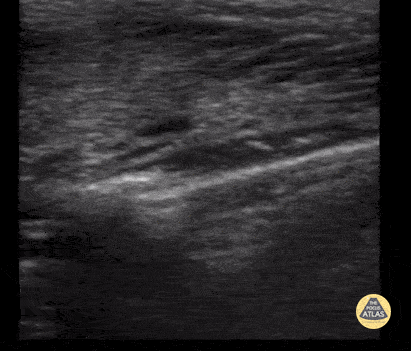

29 month old with a mild, non-displaced clavicle fracture. Note the cortical disruption seen by ultrasound with an overlying small hematoma. Contributor: Antonio Riera, MD